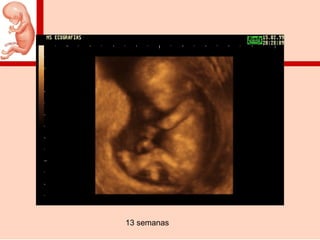

13 semanas